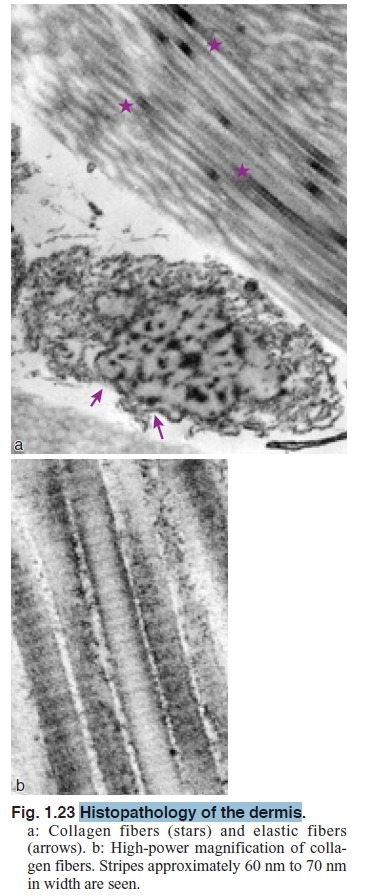

Collagen fibers account for 70% of the weight of dry dermis (Fig. 1.23) and appear white to the naked eye. The collagen

fibrous component is poorly extensible; however, it is extremely tough and especially resistant to tension parallel to the fibers. This characteristic is important in maintaining the dynamic strength of skin.

In light microscopy, the proteinaceous collagen fibers stain well in eosin solution; they stain red in Van Gieson and blue after Mallory staining. The fibril is observed by electron microscopy as being very long, 100 nm to 500 nm in diameter with cross striations that repeat at intervals of 60 nm to 70 nm (Figs. 1.23 and 1.24). Fibrils become collagen fibers by aggregating with glycoproteins. A thick collagen bundle can reach 2 mm to 15 mm in diameter.

Collagen fiber molecules are produced in the rough endoplasmic reticulum of fibroblasts. Helical procollagens with three a-chains are secreted and the molecular ends are cut by procollagen peptidase to become tropocollagens. The molecules are crosslinked to each other with a regular gap that forms the striped collagen fiber (Fig. 1.23b).

Elastic fibers are 1 mm to 3 mm in diameter. They cannot be differentiated from collagen fibers by HE staining. Elastic fibers stain dark blue to black in Weigert resorcin fuchsin, red-violet in aldehyde fuchsin, and brownish black in orcein. In elastic fibers, the characteristic striped pattern of collagen fibers is not observed by electron microscopy (Fig. 1.23). A skeletal fiber is 10 nm to 15 nm in diameter and its main content is fibrillin. The homogeneous substances are highly elastic structural proteins called elastins.